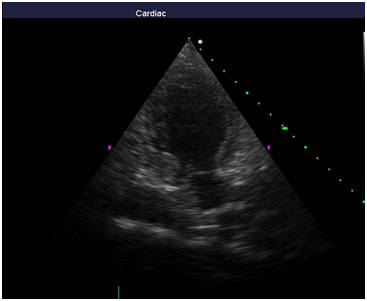

Repeated echocardiography revealed the zone of violation of local contractility (akinesis and pronounced hypokinesis) all segments on the medial and apical level with the formation of acute left ventricular aneurysm, a marked reduction of EF (23%), hyperkinesis all segments at the basal level (Figure 4-8). Troponin test was strongly positive (Figure 9). The patient is re-examined by a cardiologist, on the basis of ECG, Echo pattern, and the presence of markers of myocardial damage diagnosed with acute myocardial infarction in type 2 complicated by development of acute left ventricular aneurysm, acute heart failure Killip class IV. We carried out differential diagnosis between stress cardiomyopathy and myocarditis.

Figure 6 Echocardiography: 5АС, hyperkinesis of the basal segments with apical ballooning.